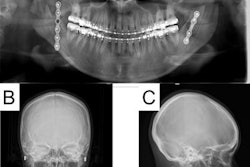

Orthodontists employ the use of CBCT imaging to accurately assess complex malocclusions. Those same scans can be used to create 3D models for further diagnosis and treatment planning.

Currently, image segmentation is the most challenging part of converting a CBCT scan to a 3D model, the authors noted. The research focused on training a promising novel algorithm, the MS-D neural network, to simultaneously segment both the jaw and teeth from CBCT scans.

The team used 28 CBCT scans acquired from patients ages 11 to 24 who were set to undergo orthodontic treatment. Four dentists with at least two years of experience segmented the scans into three classes: teeth, jaw, and background.

A CBCT scan and segmentation from one patient. The false negatives and false positives for the teeth and jaw are colored in the difference map. Image courtesy of Wang et al (2021), "Multiclass CBCT Image Segmentation for Orthodontics with Deep Learning," J Dent Res.In one example, the difference map showed the algorithm erred mostly at the edges of segmentation with a difference of about 1 pixel. The algorithm also missed some thin bony structures around the maxillary sinus, the authors noted.